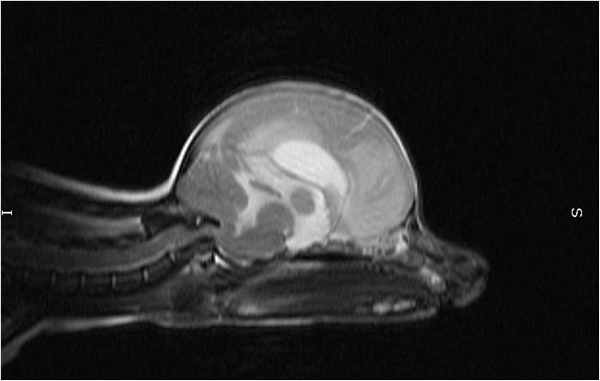

МРТ исследование пациентов с атланто-аксиальной сублюксацией

МРТ обеспечивает превосходное разрешение при исследовании нервной паренхимы и позволяет выявить другие патологии мозга, такие как дорсальную компрессию С1-С2, атланто-окципитальный оверлепинг, Киари и прочее.

Той терьер с атланто-аксиальной нестабильностью

На мрт исследовании нашего пациента – здесь представлена сагитальная Т2 взвешенная последовательность, определяется смещение аксиального позвонка в дорсальном направлении по отношению к атланту, дислокация дорсальной дужки атланта к задней черепной ямке с тяжелой компрессией как мозжечка, так и спинного мозга.